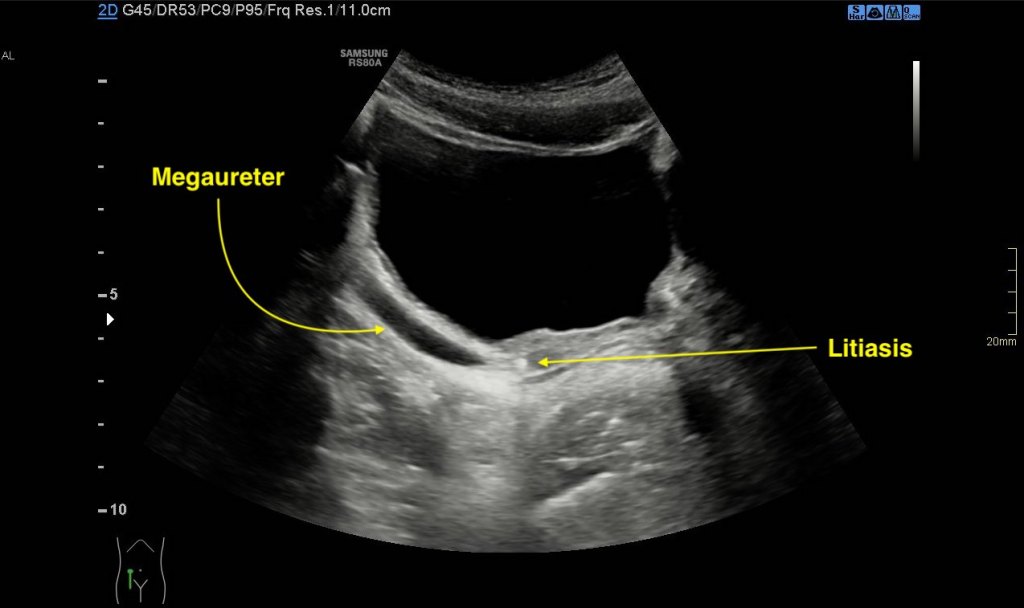

5. Megauréter:

- Dilatación del Uréter:

- En ecografía: Se observa un uréter anormalmente ensanchado.

- Medición: El diámetro es significativamente mayor que el rango normal (en niños, mayor que lo esperado para su edad).

- Ubicación de la Dilatación:

- En ecografía: Se determina si la dilatación es en la parte proximal, media o distal del uréter.

- Evaluación de Obstrucción:

- En ecografía: Se busca evidencia de bloqueo en el uréter o cerca de la unión ureterovesical.

6. Presentación Clínica:

Siempre valorar dilatación o Hidronefosis, en este caso, era normal. Nos sirve de repaso básico de Anatomía.